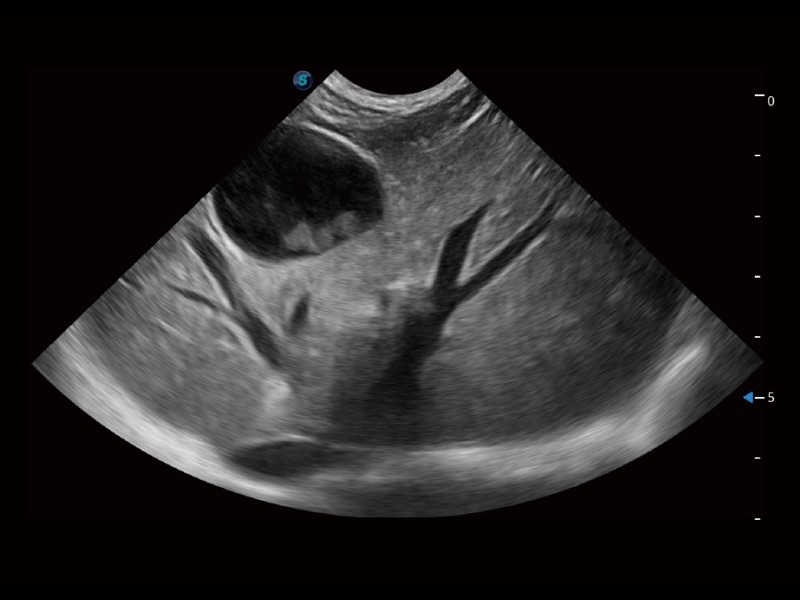

动物是人类最亲密的朋友和最值得信赖的伙伴。DB中国旗舰官方网站也一直致力于探索动物专用的超声影像解决方案。全新推出的ProPet系列,是DB中国旗舰官方网站在动物超声影像智能化、专业化、精准化的一次跨越式革新。动物不能用言语来表述自己的不适,通过超声影像,ProPet系列搭建了动物医生与不同物种沟通的“桥梁”,为动物医生注入了“治愈之力”。 ProPet 70将是您值得信赖的超声伙伴。它配备了复合材料线阵探头,帮助动物医生获得卓越精准的临床图像。同时ProPet 70直观便捷的操作体验以及专业的测量工具,可为不同体型和生理结构的动物带来全面临床评估,切实为动物医生提供智能、专业、精准的超声影像解决方案。

ProPet 70 进一步提升了微米成像算法,更加注重对基础原始图像的还原和保留,在有效减少斑点噪声、增强组织边界显示的同时,避免过度优化丟失真实的解剖信息。

ProPet 70专为动物医生设计,对不同的动物体型和生理结构作出了针对性的优化。通过动物影像专用软件,可满足个性化的应用需求,帮助动物医生获得更精确的诊断数据。

ProPet 70 全新的动物超声智能软件和丰富的探头群,为动物医生提供了高清晰度和精细分辨率的图像,无论在宠物、马科、畜牧还是实验室动物等应用中都可以轻松应对,为您的日常工作带来满意的体验。